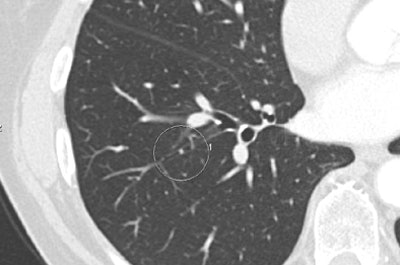

| Above, false-positive lesion detected by ICAD-L was actually mucus in bronchus. Below, true negative nodule detected by the reader and ICAD-L. Images courtesy of Dr. Peter Herzog. |